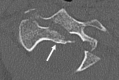

Fractures of the second cervical vertebra (C2, axis) are common in adult spine surgery. Those fractures occurring in younger adult patients are often associated with high-energy mechanism trauma, resulting in a "Hangman's Fracture." Management of these fractures is often successful with nonoperative means, though surgery may be needed in those fractures with greater displacement and injury to the C2-C3 disc. Older patients are more likely to sustain fractures of the odontoid process. The evidence supporting surgical management of these fractures is evolving, as there may be a mortality benefit to surgery. Regardless of treatment, longer-term mortality rates are high in this patient population, which should be discussed with the patient and family at the time of injury. Pediatric patients may suffer fractures of the axis, though differentiation of normal and pathologic findings is necessary and more difficult with the skeletally immature spine.